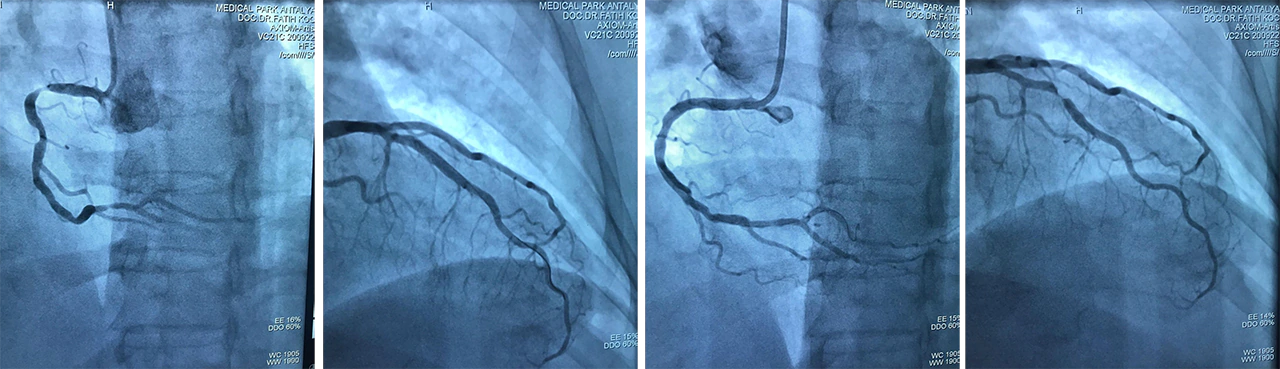

El bileğinden anjio (radial anjiografi) ve balon/stent işlemleri:

El bileğinden anjiografi ve balon/stent işlemlerinin sıkılığı dünya çapında giderek artmaktadır. Deneyimli merkezlerde yapıldığında, kanama kontrolünün kolay olması, kalıcı ve ciddi bir komplikasyona yol açmaması, kan sulandırıcı kullanan hastalarda da yapılabilmesi gibi avantajlarından dolayı hekimler tarafından giderek daha fazla tercih edilmektedir. Hastalar ise uzun süre yatış ihtiyacı olmaması, kum torbası kullanılmaması ve aynı gün birkaç saat içinde taburcu edilebilmesi gibi nedenlerden el bileğinden anjio yönteminden daha fazla memnun kalmaktadırlar. Bizde kliniğimizde anjiografi işlemlerimizi rutin olarak el bileğinden yapmakta, stent ihtiyacı olursa onu da yine el bileğinden implante etmekteyiz.